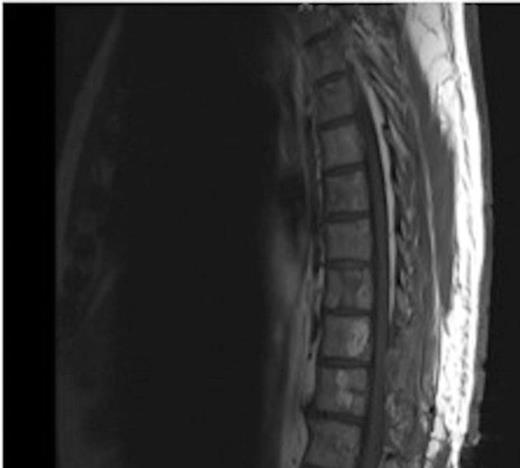

MRI showing the T10-11 extra-dural tumour with erosion of the T12 pedicle

Due to the low-grade nature of the tumour and the spinal cord compression the advantages and disadvantages of surgery versus radiotherapy were discussed with the patient who then agreed to have the tumour surgically removed.

The patient underwent a two-level decompressive thoracic laminectomy and complete macroscopical excision. An intra-operative smear exhibited carcinoid tumour characteristics.